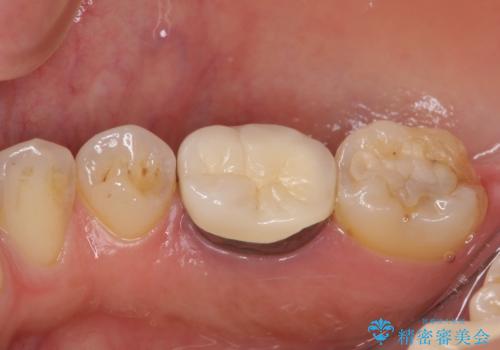

- 歯肉の退縮に伴い、金属を用いたクラウンの縁が見えてしまうことを気にして来院された患者様です。

歯肉には膿の出口が見られ、レントゲン写真からは歯根周辺に病変が認められたため、まずは根管治療を行い、その後フルジルコニアクラウンにて補綴することとしました。